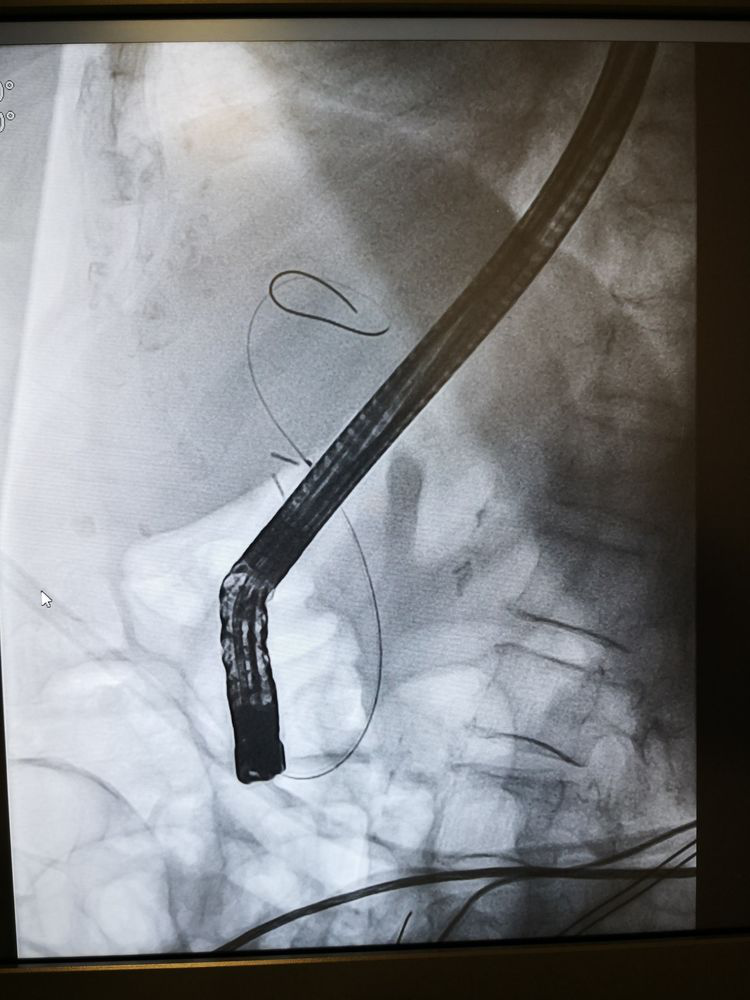

十二指腸乳頭插入切開刀(乳頭在憩室旁,增加了手術難度)。

X光下觀察導絲順利置入膽管,并造影觀察擴張的膽管,評估狹窄長度。